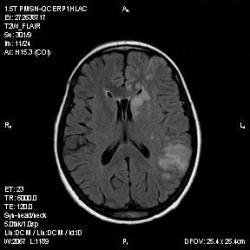

Из анамнеза - Женщина 45 лет. За год похудела на 15 кг (со слов матери), в последние месяцы случались эпизоды потери сознания. Онкозаболеваний и прочая в анамнезе нет. Сознание спутанное, из особенностей в анализах только подъем амилазы крови.

К сожалению, не владею методом КТ, но учитывая наличие неравномерного уплотнения в мозговых структурах с элементами очаговых "вкраплений", единственное, что приходит на ум - это рассеяный склероз. Хотелось бы уточнить, что беспокоило пациентку в течение последнего года кроме потери веса и эпизодов потери сознания? Была ли какая-либо очаговая неврологическая симптоматика? Отмечались ли какие-либо расстройства в двигательной или чувствительной сфере и т.д.? С уважением Helenmar.

И это точно не РС, т.к. характер очагов другой, ни один из них не копит контраст, нет субтенториальных очагов (извиняюсь, я этого в сообщении не указал), нет клиники.

"Раскрою" карты. Мы подумали о синдроме MELAS (mitochondrial encephalomyopathy, lactic acidosis and stroke) - дословно, митохондриальная энцефаломиелопатия, лактоацидоз и инсульт. В качестве дифференциальной диагностики можно было бы предположить вирусный энцефалит, но опять-таки, расположение очагов смущает - только с одной стороны и в абсолютно различных структурах.

В данном случае мы видим импульную последовательность FLAIR - режим с подавлением сигнала от воды, поэтому ликвор гипоинтенсивен, а также (вторая серия) - изображения, взвешенные по T1 после введения контрастного препарата. На T1 жидкость (ликвор) также представляется гипоинтенсивной. Зато на этих сериях гиперинтенсивны сосуды, т.к. контрастное вещество циркулирует в кровяном русле.

Изменения носят сосудистый характер. Процесс достаточно острый, имеется объемное воздействие, борозды левой гемисферы компремированы. По поводу MELAS синдрома очень сомневаюсь, почему поражена только левая гемисфера? Надо делать МР-ангиографию, смотреть нет ли стеноза

MELAS синдром - дебютирует с детских лет, характерен целый комплекс неврологических проявлений, заболевание генетическое, поражение системное, хотя есть множество вариантов митохондриального поражения, все же сомнительно. Хотелось бы акцентировать внимание, что гиперинтенсивные очаги есть в мозолистом теле, поражены выражено перивентрикулярные отделы, U -пути, белое вещество, поэтому так категорично демиелинизацию не вычеркивала бы из дифряда ( хотя тоже нетипично односторонее поражение). Думаю, для объективных выводов все же мало общей информации о пациентке, были ли клинические эпизоды раньше, чем объяснить такую потерю веса (возможно есть проявление паранеопластического синдрома?). Ну и МРТ-контроль в динамике, ангиография.

Да, неоднозначный случай. Точно не РС и не ОНМК. Я бы написала асимметричную лейкоэнцефалопатию неясного генеза. Можно было бы думать о лимфоме (полифокальное поражение, да еще мозолистое тело вроде бы задействовано (эх, сагиттальчики бы)). Но! Учитывая отсутствие накопления КВ.... Ну и надо исключать интоксикацию, всяческие аутоиммунные процессы (в т.ч. и васкулиты), сахарный диабет, ну и естественно наследственную патологию обменных процессов. УУУх! Вот.......

Имхо ишемический онмк в бассейне сма. Особенно показательны 5-й и 6-й файлы, отграничение как раз на границе бассейнов средней и перикаллёзной. Плюс одностороннее поражение.